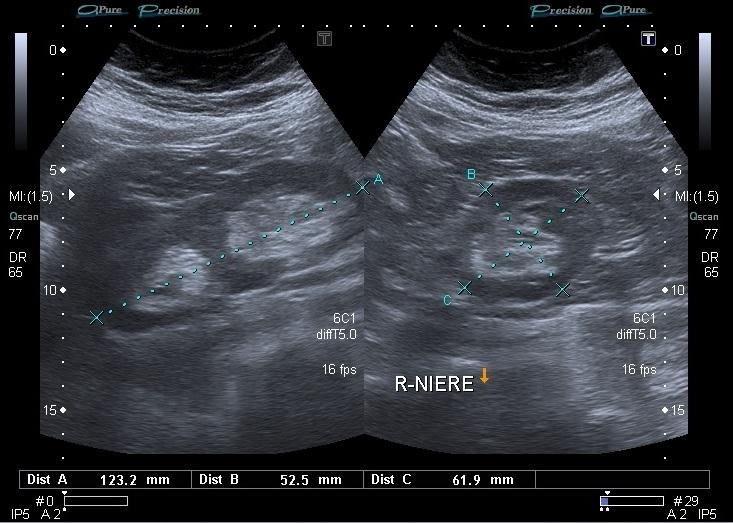

30 year old male presents for a renal ultrasound

liver & spleen cysts

Adult Polycystic Kidney Disease